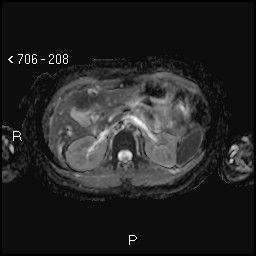

image

Aspetti RM: minuto nodulo della testa pancreatica ipointenso in T1.